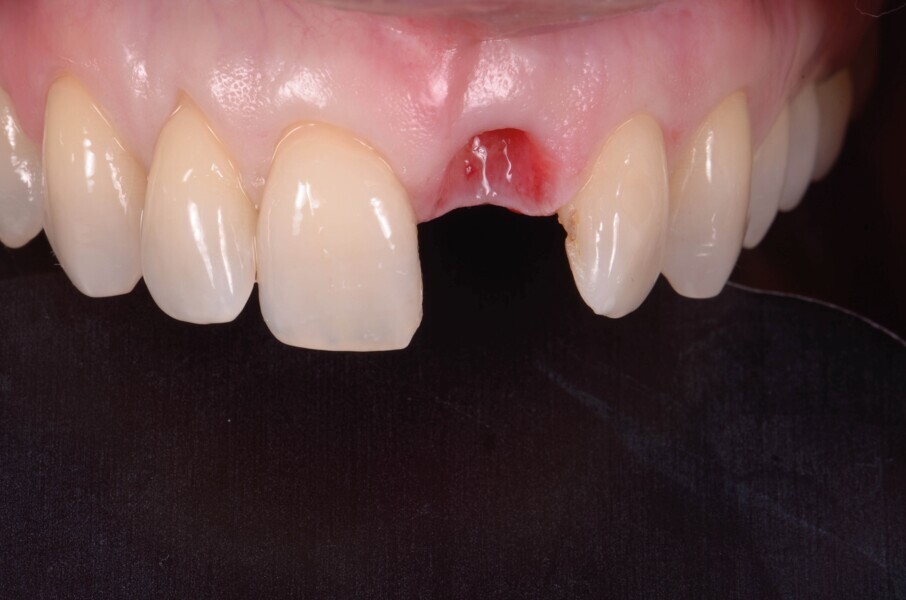

Une patiente de 42 ans est adressée au cabinet pour le remplacement de son incisive centrale supérieure gauche (dent 21) qui est à l’origine de douleurs. Un antécédent de traumatisme dentaire remontant à l’adolescence est rapporté. La ligne du sourire de la patiente est normale, mais la dent 21 est égressée (Fig. 1) La gencive présente un biotype raisonnablement épais et le feston gingival est très marque.

Fig. 2a : Vue préopératoire intraorale

Une fistule avec écoulement purulent est présente en regard de l’apex de la dent. Une tomodensitométrie volumique a faisceau conique (CBCT) est réalisée pour évaluer l’environnement péri-dentaire : l’épaisseur de l’os vestibulaire, la forme de l’alvéole et la position de la racine sur le plan sagittal (Figs. 2–3). Une fracture radiculaire est mise en évidence.

L’endodontiste chez qui la patiente a d’abord été référée a émis un pronostic peu favorable en raison d’une déhiscence osseuse importante en vestibulaire, associée à une fenestration au niveau de l’apex. L’espace inter occlusal est réduit, avec un profond recouvrement incisif. La décision de ne pas conserver cette dent est alors prise. Le choix se porte vers une restauration unitaire implanto-portée.

Dans le cas de la patiente, les tissus mous sont bien positionnés : la dent a subi une égression, mais aucune récession n’est présente. L’os vestibulaire est partiellement absent et classe l’alvéole dans le type II selon Elian et al.2